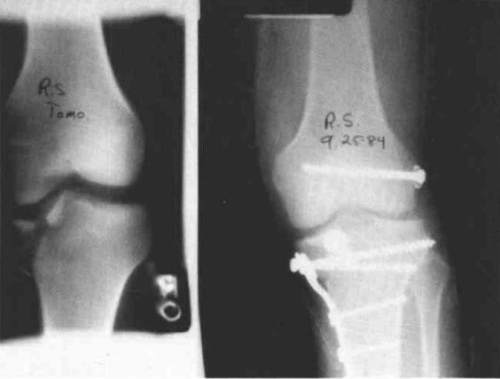

A twenty-nine year old male sustained a high caliber gunshot wound to the left knee (Fig. 4), traversing the lateral femoral condyle through the joint space and through the lateral tibial plateau. Open reduction internal fixation (ORIF) and ligamentous repairs were made. Postoperatively, the patient was placed in a standard cast brace due to the inability to provide adequate medial-lateral stability of the knee surgically (Fig. 5). The cast brace was attached to a continuous passive motion dynamic suspension system to restore and maintain motion (Fig. 6). At the time of the initial cast bracing, the patient had considerable soft tissue edema about the knee. The use of passive motion quickly reduced that swelling to the point where the cast brace provided little support. After one week, the cast brace was reapplied with the addition of a varus producing strap (Fig. 7) and the patient began ambulation training and was discharged. (If atrophy or swelling should continue, the varus producing strap can be easily adjusted to maintain force on the knee and another cast change would not be required).

Case 2

A twenty-five year old female sustained a fracture dislocation of the left knee (Fig. 8). The fracture and ligaments were internally fixed, and the patient was placed in a continuous passive motion dynamic suspension system utilizing a Mobilizing Brace (3 D) and a bootie (Fig. 9). The patient achieved 0-90° of motion in two days and was maintained in passive motion for five days until she could achieve the same range of motion actively without excessive pain. The patient was then cast braced for increased medial-lateral stability, received gait training, and was discharged from the hospital.